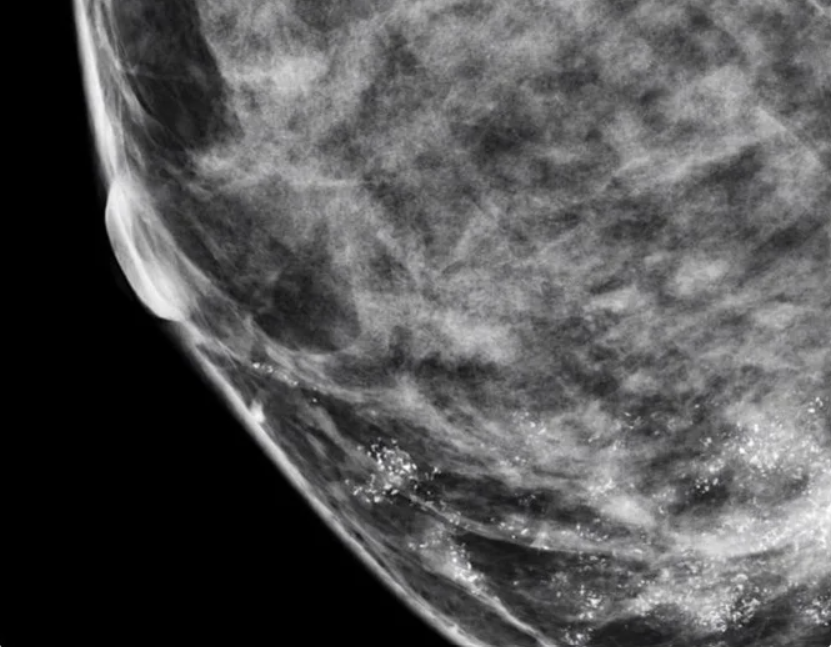

Доброкачественные микрокальцинаты

На маммографическом изображении они выглядят как мелкие белые точки или узоры, чаще всего множественные и рассредоточенные.

Для доброкачественных кальцинатов характерны четкие округлые контуры, похожесть друг на друга (мономорфность) и равномерность распределения. К факторам, указывающим на доброкачественные микрокальцинаты, также относится их малый размер, отсутствие изменений в окружающих тканях и отсутствие быстрого роста в динамике.